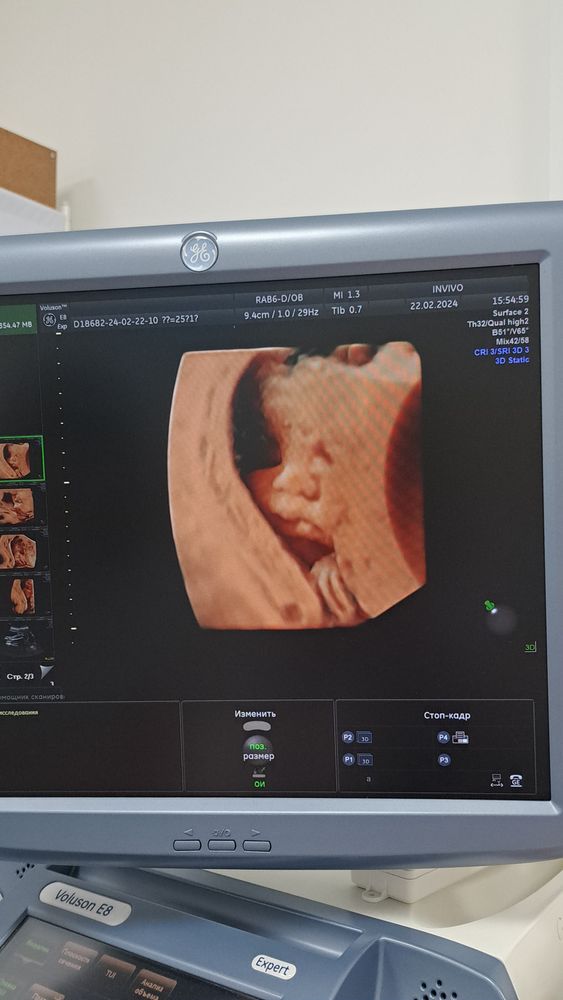

Мой 3 пупсик))))

И он так нам с мужем напомнил нашего пока младшенького🩵🩵🩵

Опять мальчик🙉 Привет декрет)))))))